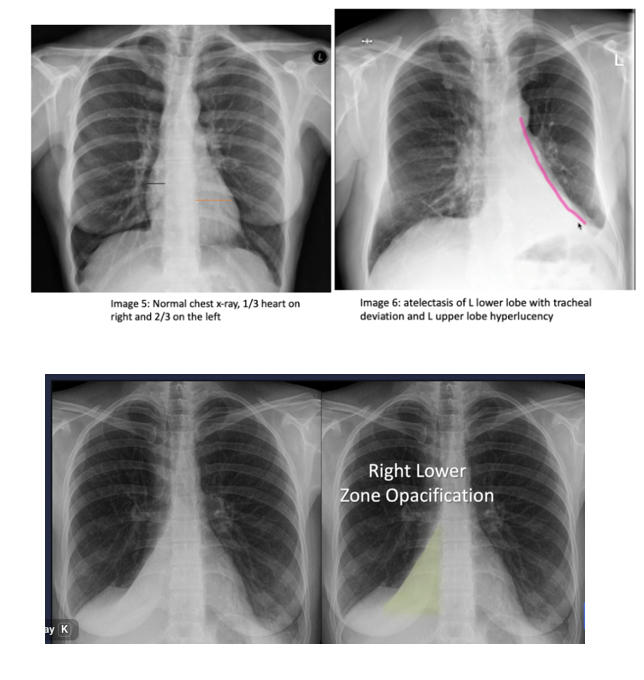

diagnosing atelectasis

chest Xray: colume loss, shift of fissuresm elebated hemidiaphram

atelactasis

collapse of alveoli leading to reduced gas exchange